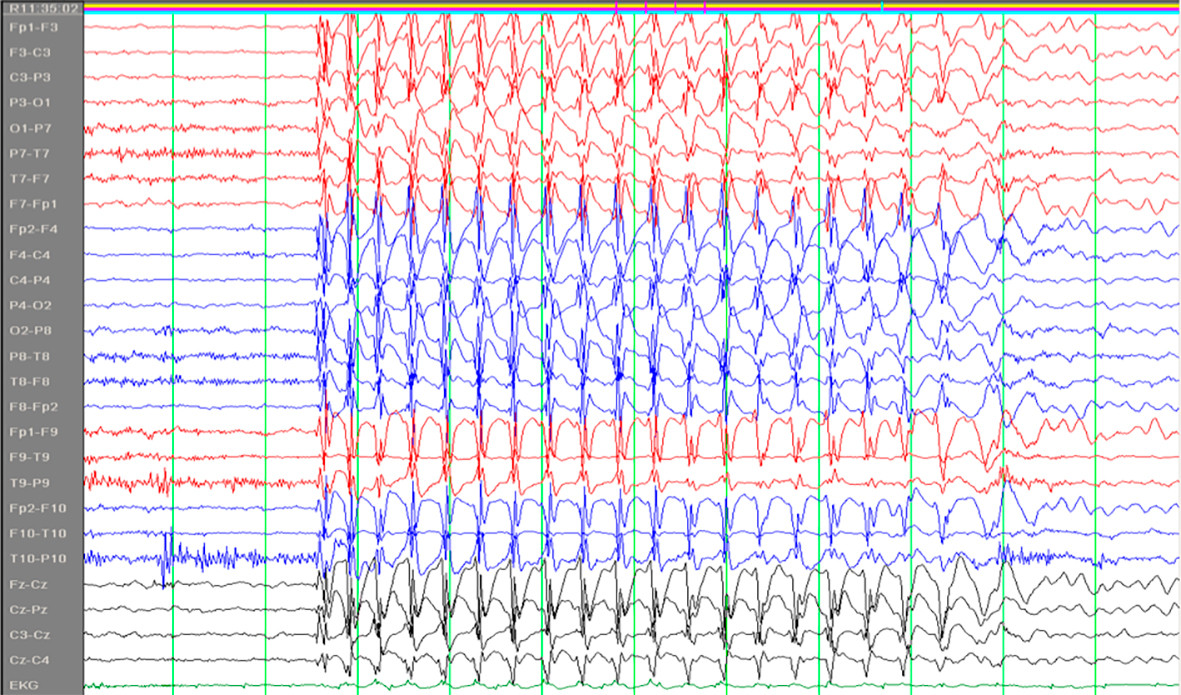

Absenser er en type epileptiske anfall som kan ses ved flere generaliserte epilepsiformer, først og fremst ved absensepilepsi i barnealderen. Ordet stammer fra det franske absence og det latinske absentia og kan oversettes med åndsfravær. Barna blir i noen sekunder fraværende i sin virksomhet eller tale, uten at vedkommende selv merker det. De får et tomt, stirrende blikk. Det er ingen kramper, men av og til ses diskrete rykninger i øyelokkene. Det er viktig at foreldre er oppmerksomme på slike tilfeller hos barn. Absensene har et spesifikt EEG-korrelat; 3/sekund «spike-waves» (fig 1) (1).